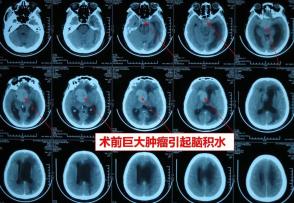

下面这位患者由于早期没有及时就诊,垂体瘤巨大导致脑积水,发生意识不太清楚,双眼几乎失明才就诊。

巨大肿瘤经努力顺利全切,遗憾的是病人术后在肿瘤腔以外的地方发生广泛性脑出血,进一步导致脑肿胀发生死亡。

这样的肿瘤又不能只切除一部分,因为只切除一部分,同样也会发生出血,并且残余的肿瘤组织更容易出血。

因此及时就诊,早期发现是最关键的。